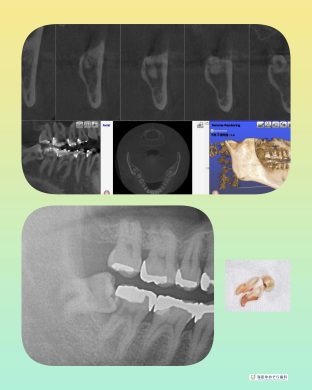

横向き親知らずの抜歯症例

最近の症例

院長はこのような横向きに埋まっている抜歯ケースも

1000症例以上の手術実績あり☆

横に埋まっている場合はCT撮影で安心です☆